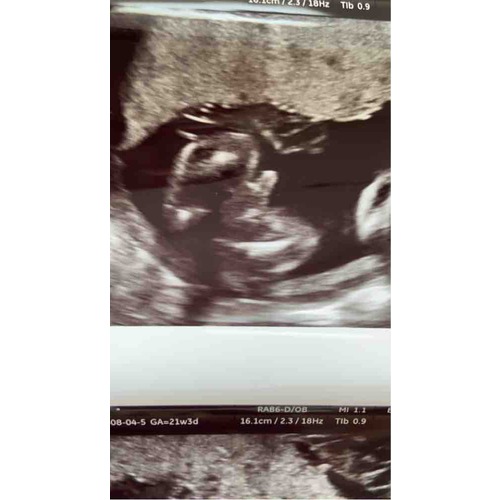

Ja hoor hier hetzelfde verhaal! Eerst een meisje met 16+3 en met 19+1 een jongen ! Ik ben toen naar een ander echo centrum geweest voor een second opinie met 21+3 en daar echt 100% een jongen gezien!

Komt vaker voor. Jongetjes ontwikkelen zich soms later pas waardoor je het piemeltje niet ziet. In beginsel lijkt elke baby een meisje. Rond 14 weken bestaat inderdaad de kans dat hij nog niet zo ver ontwikkeld was. Zie dat je echo met 19 weken is, dan is het idd al wel af.

Ik zou zeggen dat je een zoontje krijgt oo basis van de echo’s.